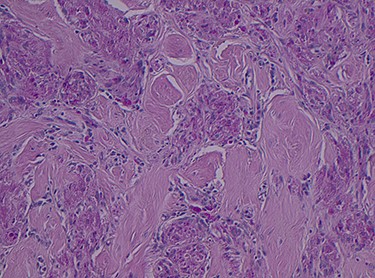

Histopathology of the right hemicolon found five firm nodules in the caecum and an additional seven polyps in the ascending colon macroscopically. Microscopically, a total of eight lesions in the caecum and ascending colon were found to be GCTs, varying in size from 1 to 7 mm. They were submucosal with intact covering mucosa (Figs 1 and 2). Tumour cells had periodic acid-Schiff (PAS)-positive granular cytoplasm and small nucleoli (Fig. 3). Immunohistochemical staining was positive for S-100 (Fig. 4) and inhibin. Twenty-four lymph nodes identified showed no abnormality. Spindling was seen in some tumours in this case, but overall, there are less than three worrisome features, and as such, these GCTs were considered atypical. Other polypoid lesions identified included two hyperplastic polyps and a submucosal lipoma.

Histologically GCTs are characterized by plump neoplastic cells with abundant eosinophilic granular cytoplasm. Immunohistochemistry for neural markers, S-100 protein and NSE are diffusely positive, while other markers include inhibin, calretinin and nestin [2, 4]. Fanburg-Smith et al. [3] described microscopic criteria to predict malignant potential, where GCTs meeting three or more criteria were classified as histologically malignant.